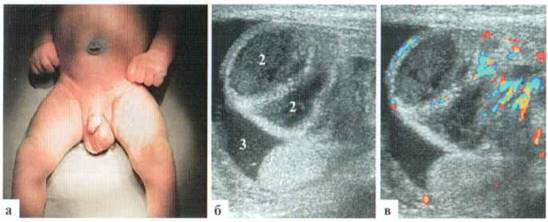

Рис. 2.1.2. Крупные размеры трансформированной гидатиды: 1 — яичко, 2 — гидатида. Размеры яичка и гидатиды практически одинаковы. Сосудистый рисунок при ДДС в гидатиде не прослеживается (б)